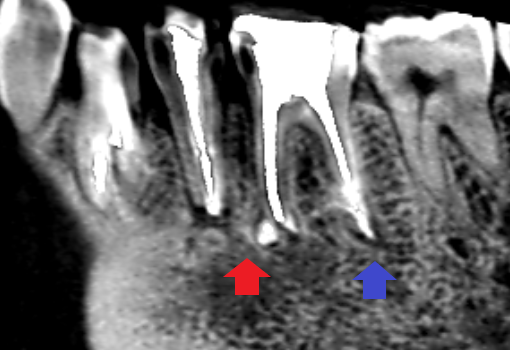

膿の改善をはかるべく、下顎第二小臼歯と下顎第一大臼歯の精密再根管治療を行いました。画像は、根管充填のレントゲン画像です。根管充填はMTAセメントを用いて行いました。下顎第二小臼歯と下顎第一大臼歯共に根の先までしっかり根管充填できています。特に下顎第一大臼歯の近心根と遠心根は、それぞれの根に2本ずつ根管があり、2本の根管を結ぶ通路であるイスムスを除去し根管の隅々まで感染が残らないように留意しました。